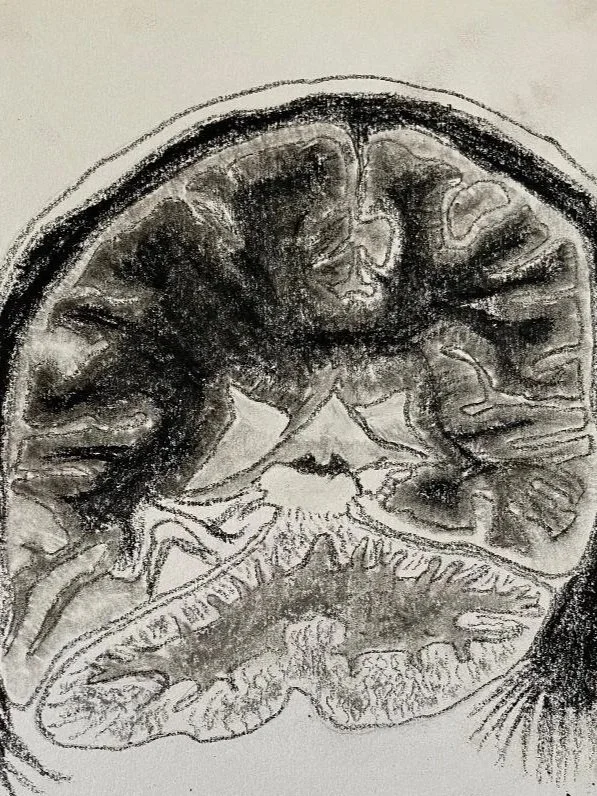

Normal MRI of the brain - 9-year-old